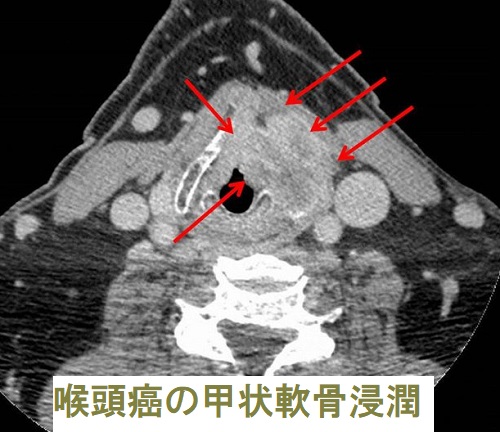

喉頭癌における最大のリスクファクターは喫煙です。リスクファクターの共通する口腔癌、下咽頭癌、肺癌、食道癌は重複癌として発生する可能性が高い。喫煙がリスクファクターでない甲状腺癌・子宮体癌(子宮内膜癌)の重複は、

である可能性高い[Oncol Lett. 2013 Oct 15;6(6):1616–1618.]。甲状腺癌と喉頭癌の重複癌は稀とされます。

下咽頭癌は、

- 高齢男性に多い

- 扁平上皮癌

- 喉頭がん・食道がんと同じく飲酒と喫煙がリスクファクター

特に下咽頭癌と食道癌は重複しやすいので、一方の癌が見つかったときはスクリーニング検査が必要。 - 頸部リンパ節転移を生じやすく、無痛性の徐々に増大する頸部腫瘤で発症する事がある

などの特徴があります。